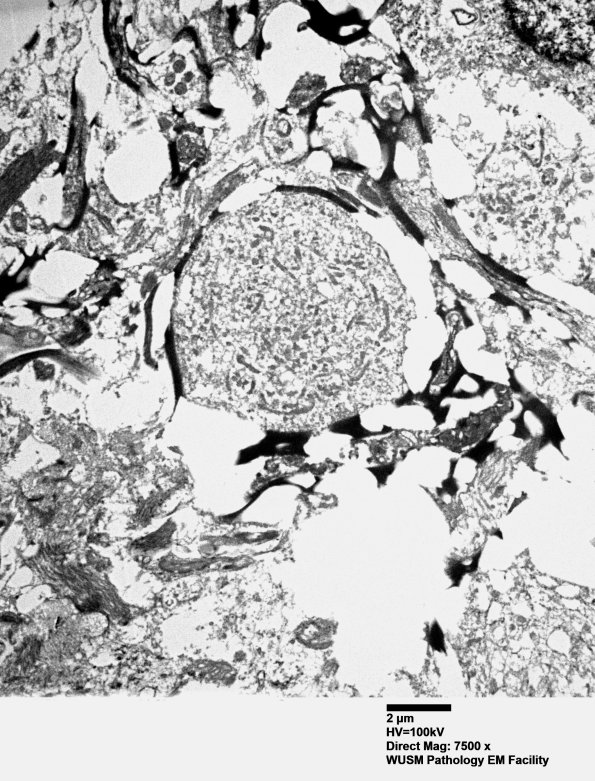

Dilated axons containing axonal cytosomes. (electron micrographs) ---- Since starting steroids, then PLEX and IVIG she has shown remarkable clinical improvement.